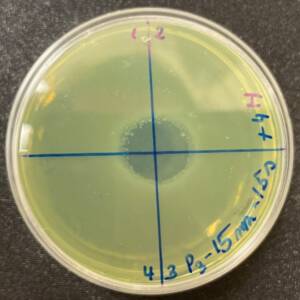

Photos of the Petri plates, 72 hours after bacterial (Pseudomonas aeruginosa) inoculation.

Image (B) is the control plate. The blue lines divide the plate into quadrants.

Photos of the Petri plates, 72 hours after bacterial inoculation. Both plates show complete (positive) bacterial growth inhibition (full translucency) at the treatment site after two UV-C doses of 15 seconds at a 15 mm distance. The blue lines divide the plate into quadrants.